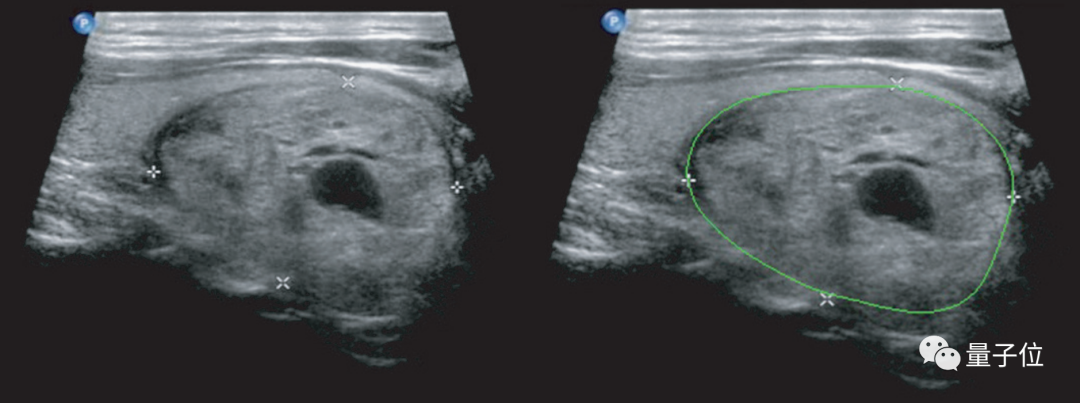

其實(shí)早在數(shù)年前,浙江大學(xué)和德尚韻興就曾與英特爾公司合作,用至強(qiáng)CPU和英特爾的軟件優(yōu)化工具開(kāi)發(fā)過(guò)深度學(xué)習(xí)模型,用于在臨床分析甲狀腺的超聲波影像。

△?使用深度學(xué)習(xí)進(jìn)行的甲狀腺結(jié)節(jié)檢測(cè)和定性診斷(右)

這種AI輔助診斷的準(zhǔn)確度,當(dāng)時(shí)就已經(jīng)比中國(guó)甲等醫(yī)院的放射科醫(yī)生至少高出10%。

當(dāng)然,這并不是說(shuō)醫(yī)學(xué)影像AI應(yīng)用會(huì)取代醫(yī)生,而是讓影像科醫(yī)生在輔助下能有更高的工作效率,也可以讓經(jīng)驗(yàn)豐富的醫(yī)生專注于更復(fù)雜的病例。